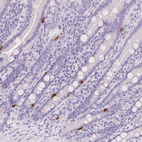

Immunohistochemistry analysis in human adrenal gland and pancreas tissues using HPA063797 antibody. Corresponding SLC18A1 RNA-seq data are presented for the same tissues.